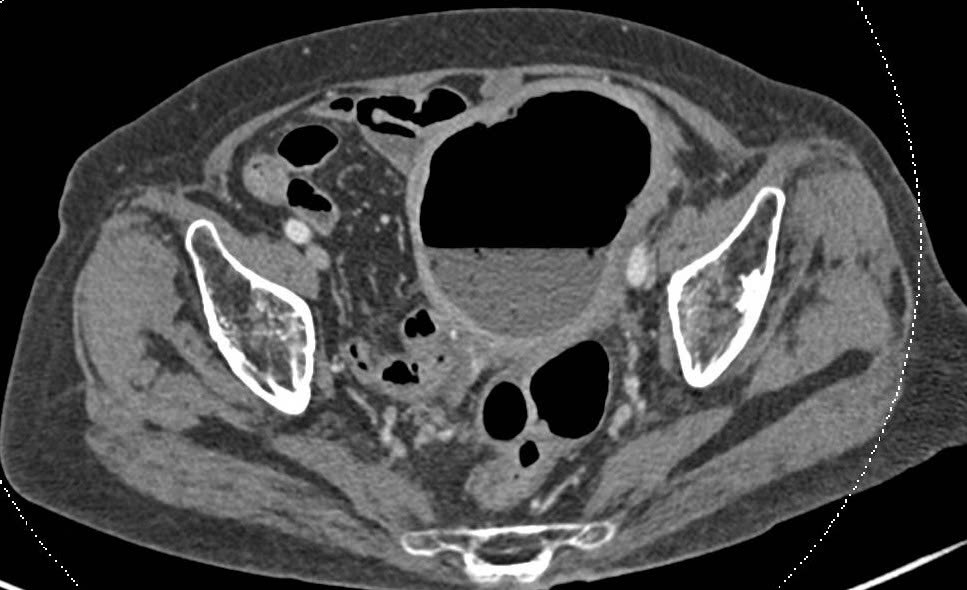

Mrs M.T.M., an 88-year-old patient from Ho Chi Minh City, was admitted to FV Hospital by her family in a condition marked by fever, persistent dull abdominal pain, and purulent vaginal discharge. Dr Le Duc Tuan, MSc, from the General Surgery Department, ordered a CT scan of the abdomen. Imaging revealed an abnormally enlarged uterus containing both fluid and gas.

Further diagnostic investigations, including colonoscopy and uterine cavity endoscopy, were subsequently performed. The results confirmed the presence of faecal matter within the uterine cavity, providing clear evidence of a rectovaginal fistula. Without timely intervention, this condition posed a significant and potentially life-threatening risk to the patient.

Dr Tuan explained that the patient’s colon contained numerous diverticula extending up to 25 cm in length, caused either by a congenital condition or long-standing chronic constipation. This resulted in faecal retention, leading to infection, inflammation, and the formation of a severe abscess, which ultimately caused the development of a colorectal fistula.